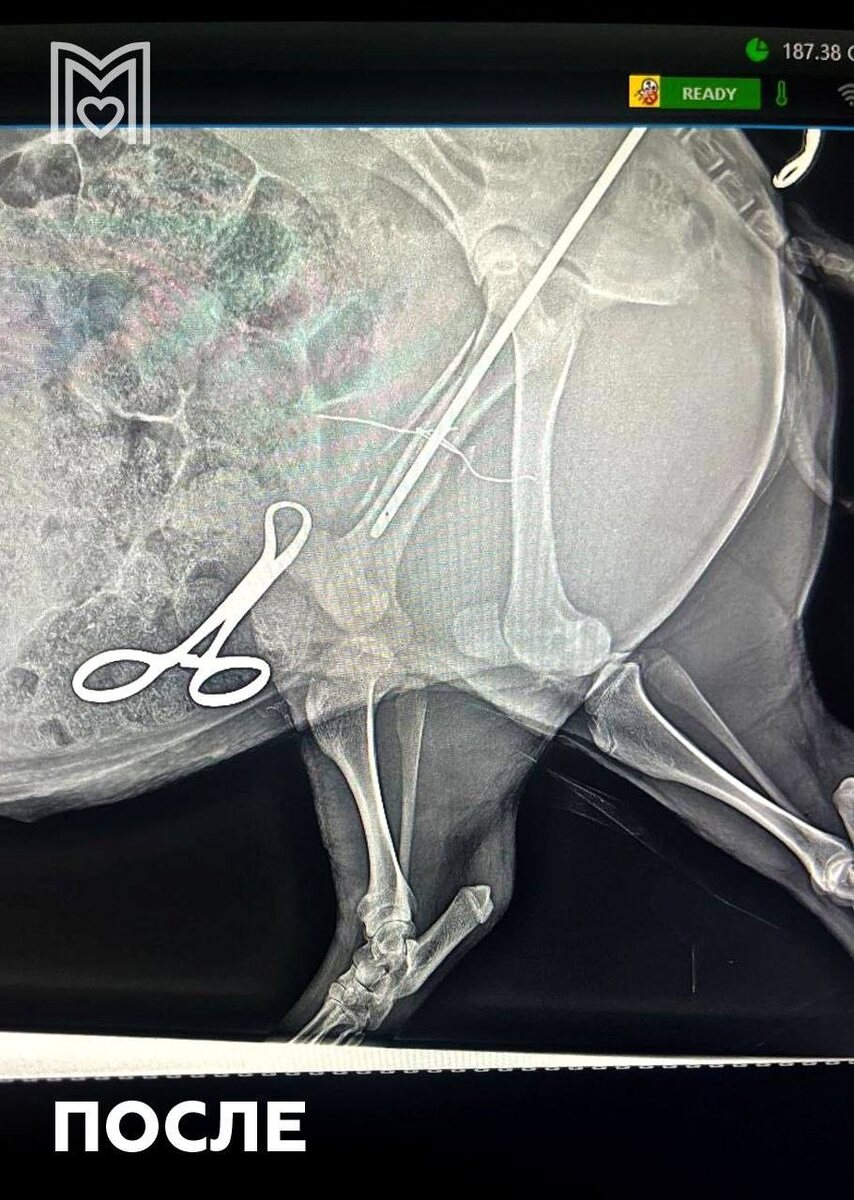

Π‘Π²ΠΈΠ½ΠΊΠ° ΠΏΠΎΠΏΠ°Π»Π° Π² ΠšΡƒΠ½Ρ†Π΅Π²ΡΠΊΡƒΡŽ Π²Π΅Ρ‚ΠΊΠ»ΠΈΠ½ΠΈΠΊΡƒ с Ρ…Ρ€ΠΎΠΌΠΎΡ‚ΠΎΠΉ β€” Π΅ΠΉ диагностировали ΠΏΠ΅Ρ€Π΅Π»ΠΎΠΌ, ΠΏΡ€ΠΈΡˆΠ»ΠΎΡΡŒ Π΄Π΅Π»Π°Ρ‚ΡŒ ΠΎΠΏΠ΅Ρ€Π°Ρ†ΠΈΡŽ.

Элвису соСдинили ΠΊΠΎΡΡ‚ΡŒ с ΠΏΠΎΠΌΠΎΡ‰ΡŒΡŽ мСталлоконструкции, ΠΎΠ½ Ρ…ΠΎΡ€ΠΎΡˆΠΎ пСрСнёс Π²ΠΌΠ΅ΡˆΠ°Ρ‚Π΅Π»ΡŒΡΡ‚Π²ΠΎ ΠΈ послС Π½Π°Ρ€ΠΊΠΎΠ·Π° отправился Π΄ΠΎΠΌΠΎΠΉ.